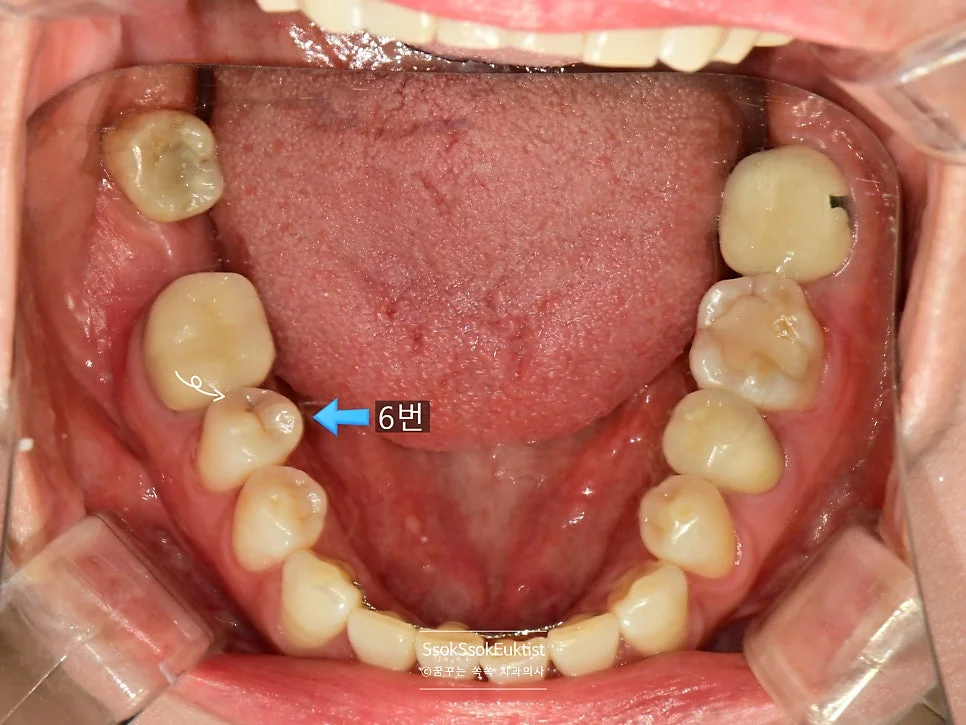

치료 전 구강 정면 — 겉으로는 큰 이상이 보이지 않지만 치아 사이에 충치가 숨어 있습니다

구강 사진에서 하얀색 화살표는 충치의 위치를, 파란색 화살표로는 해당 치아를 번호로 기재하였는데요. 각 치아의 치료 계획에 대해 말씀드리겠습니다.

- 2번 치아 → 충치가 있는 면과 기존 수복물을 모두 포함하는 치료 → 크라운 치료

- 1번 치아 → 2번 치아의 크라운 치료 시 인접한 면을 육안으로 확인 후, 치료가 필요한 만큼 충치가 있다면 레진으로 간단히 치료 (충치가 없으면 치료 X)

- 3번 치아 → 충치가 있는 면과 기존 수복물을 모두 포함하는 치료 → 크라운 치료

- 4번 치아 → 3번 치아의 크라운 치료 시 인접한 면을 육안으로 확인 후, 충치가 있다면 레진으로 간단히 치료

- 5번 치아 → 충치가 있는 면이 인접한 치아에 의해 막혀 있으므로 → 인레이 치료

- 6번 치아 → 충치가 있는 면이 인접한 치아에 의해 막혀 있으므로 → 인레이 치료

조금 어려울 수 있습니다만 천천히 설명드리겠습니다!

총 크라운 2개, 인레이 2개, 레진 가능성 치아 2개, 사랑니 발치 1개입니다.